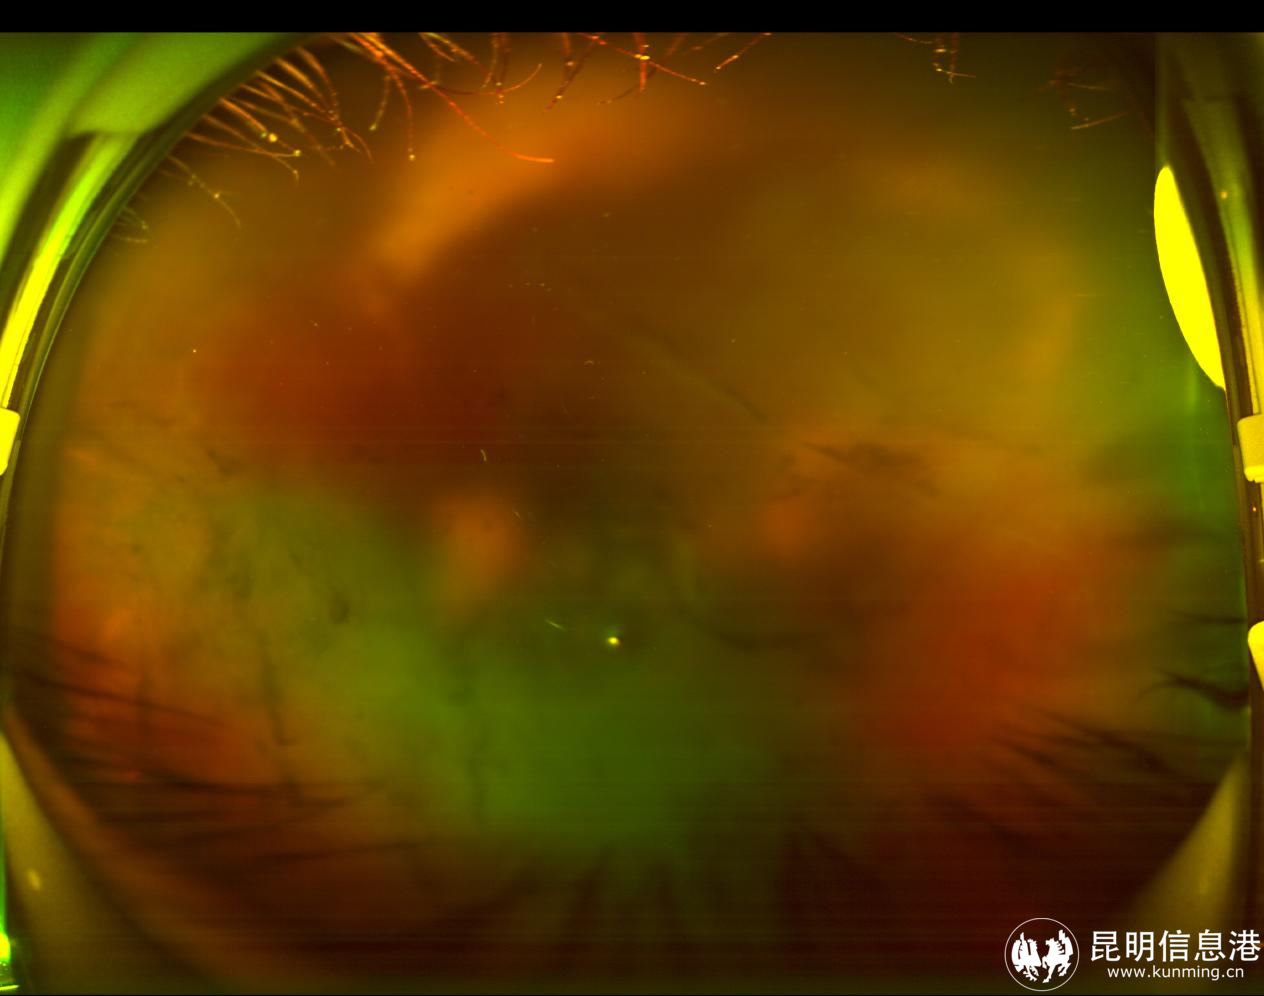

图为眼底彩图(术前):玻璃体积血后眼底细节窥不清 昆明艾维眼科医院供图